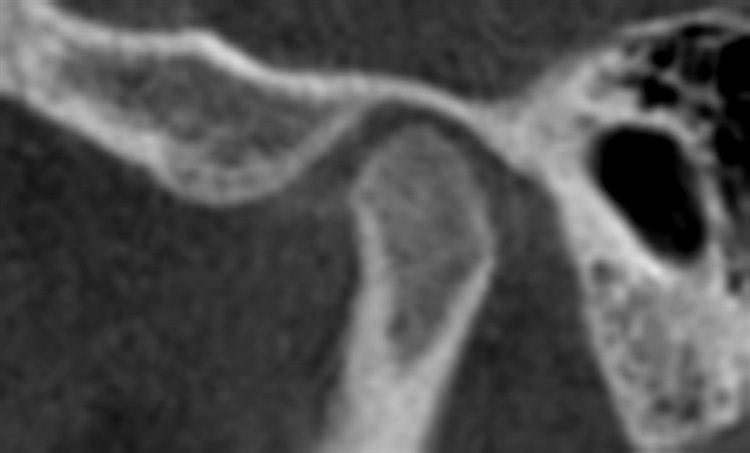

Kjeveleddsosteoartritt, jente 13 år. Foto: Avdeling for kjeve- og ansiktsradiologi, UiO/ODBetydningen av stress